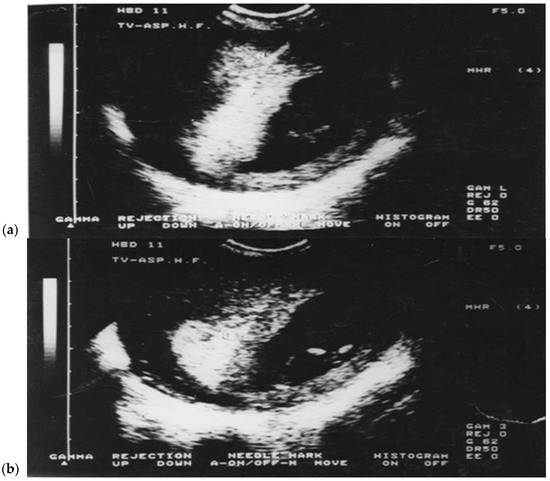

TC-CVS was conducted with the patient in the lithotomy position. Aspirations were performed at 10 to 13.6 weeks of gestational age. To perform the aspiration, we used a 26 cm long Portex catheter or a 24 cm long Holzgreve-Angiomed catheter, with continuous real-time ultrasonographic guidance provided using a Voluson 8 or 10 scanner, with a 5–9 MHz transducer. The catheter was inserted via cervix into chorion frondosum, rotating the catheter to aspirate the tissue into a 20 mL plastic syringe prefilled with 5 mL of culture medium. Amounts of 1 to 25 mg of chorion frondosum tissues were obtained and the modified short term-culture (overnight), with modification, was used in all cases for karyotyping [19,20,21,22,24,25,26,27,29,30,31,32,33]. On the other hand, TA-CVS was performed with the patient in the supine position, utilizing a single a 20-gauge-90 mm spinal needle. After disinfecting the anterior abdominal wall and ensuring the patient’s bladder was empty, the needle was inserted under continuous ultrasound guidance into the central region of the chorion frondosum. The insertion angle was gradually adjusted by 20 to 40 degrees as needed, and tissue was aspirated under negative pressure into a 20 mL syringe prefilled with the designated culture medium. Furthermore, TV-CVS was performed with the patient in the lithotomy position. To perform aspiration, we used a 35 cm long 20-gauge needle with continuous real-time ultrasonic guidance provided with a 5–9 MHz vaginal transducer with a guide needle. The needle was inserted through the fornix (anterior or posterior) into chorion frondosum (Figure 1a,b) and 20 mL syringe was used to aspirate the tissue by combining repeated strong suction and slow backward and forward movement of the needle tip. After two failed passes, for all three techniques the women were offered another CVS session a week later. All 5500 early CVS procedures were performed by a single operator (M.P.).

Figure 1.

(a,b) Transvaginal chorionic villus sampling (TV-CVS) performed at 11 weeks of gestation. The biopsy route in TV-CVS is notably longer compared to the transabdominal approach (TA-CVS). Source: Authors.